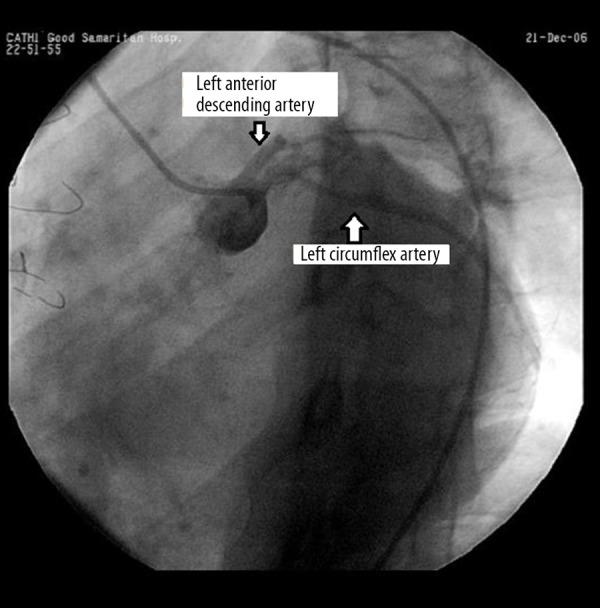

A 41-year-old man with Holt-Oram syndrome presented with seizure-like activity and was found to have an underlying conduction disturbance. Physical exam showed bilateral atrophic upper extremities with anatomic disfiguration, and weakness of the intrinsic hand muscles. Cardiovascular exam revealed a slow heart rate with irregular rhythm. EKG showed sinus arrest with junctional escape rhythm. Cardiac catheterization revealed coronary anomalies, including absent left main coronary artery and separate ostia of the left anterior ascending and left circumflex coronary artery. Coronary arteries were patent. Following electrophysiology study, sick sinus syndrome and AV block were diagnosed, and the patient received implantation of a permanent pacemaker.

一名41岁患有Holt-Oram综合征的男性出现癫痫样发作,发现有潜在的传导障碍。体格检查显示双侧上肢萎缩并伴有解剖结构变形,手部固有肌肉无力。心血管检查发现心率缓慢且心律不齐。心电图显示窦性停搏伴交界性逸搏心律。心脏导管检查显示冠状动脉异常,包括左冠状动脉主干缺如以及左前降支和左旋支冠状动脉开口分离。冠状动脉通畅。电生理检查后,诊断为病态窦房结综合征和房室传导阻滞,患者接受了永久性起搏器植入。